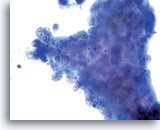

Tumor diathesis may be present and appears as a “woven shroud” with a denseness or linear presentation of debris in the center and a frayed or pulled out appearance of the material around the edges of the group. 60x

Endometrial adenocarcinoma 60x